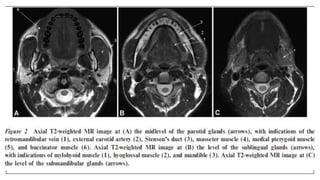

Normal anatomy

Pathologies